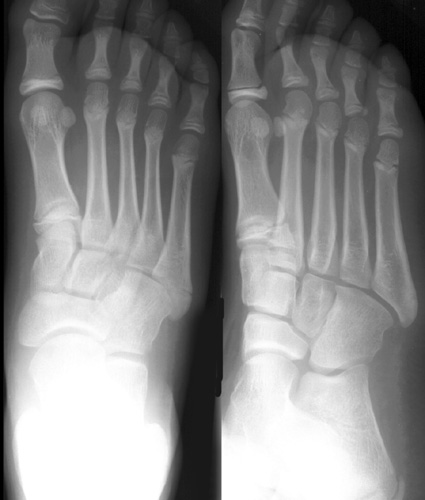

• It is important to remember that a fracture may only be visible on one view. Therefore, a careful look at each metatarsal in each view is necessary.

Look at the following radiographs. Can you find the fractures?

Click on the image for the answer.